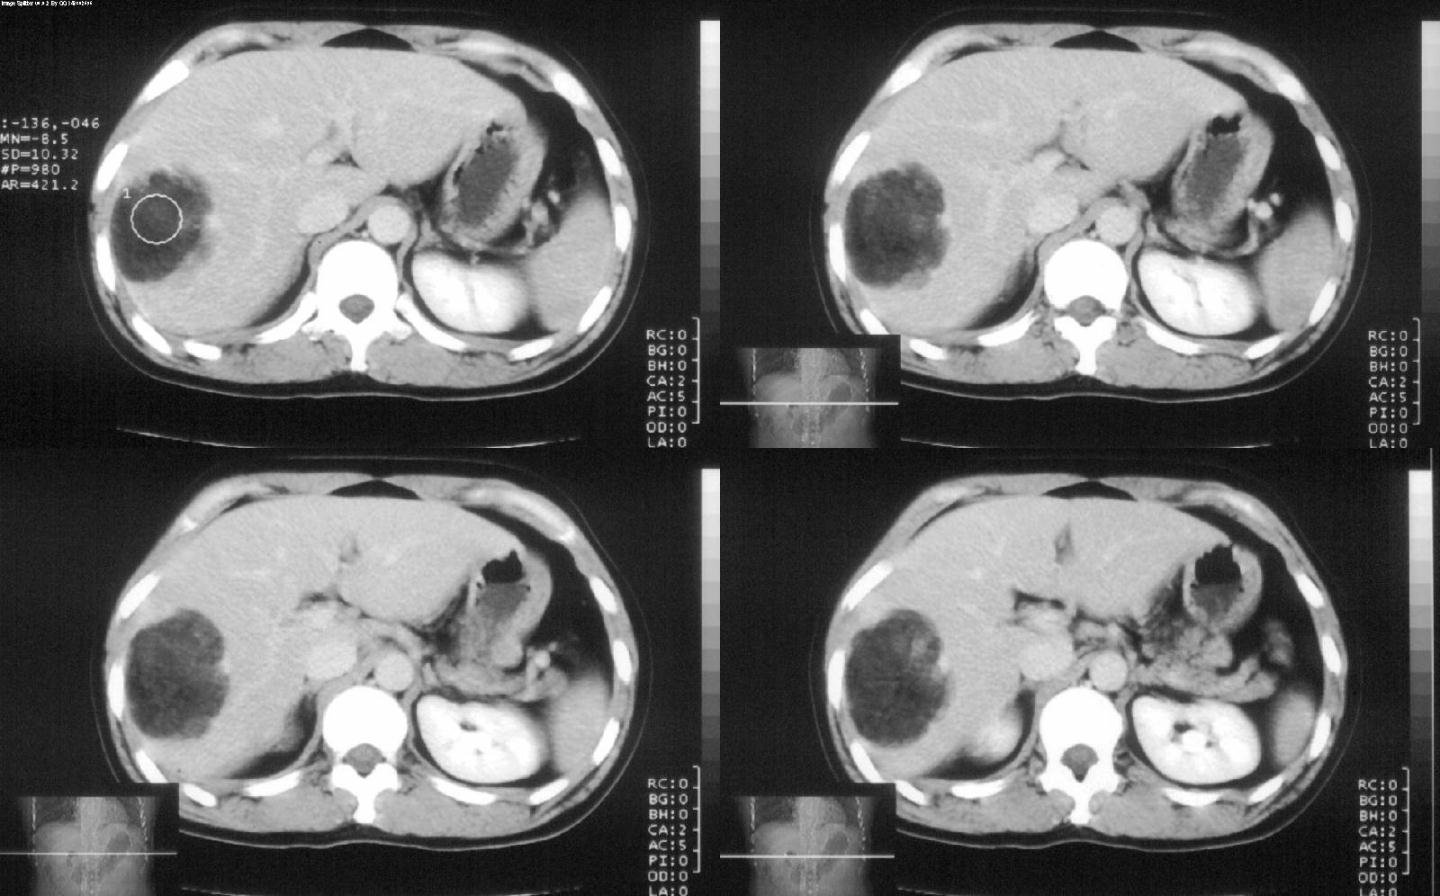

标题: CT28180:女性,42岁。体检时发占位。 [打印本页]

标题: CT28180:女性,42岁。体检时发占位。

ct值?肝脏血管平滑肌脂肪瘤

血管平滑肌脂肪瘤可能性大

考虑hcc>肝脏血管平滑肌脂肪瘤>肝脏髓脂瘤等,期待结果。

肝脏血管平滑肌脂肪瘤,边界结节样血管影持续性强化。

病灶多种成分,以脂肪为主,可见强化的血管肌肉成分,边界较清晰,综合考虑血管平滑肌脂肪瘤可能性大